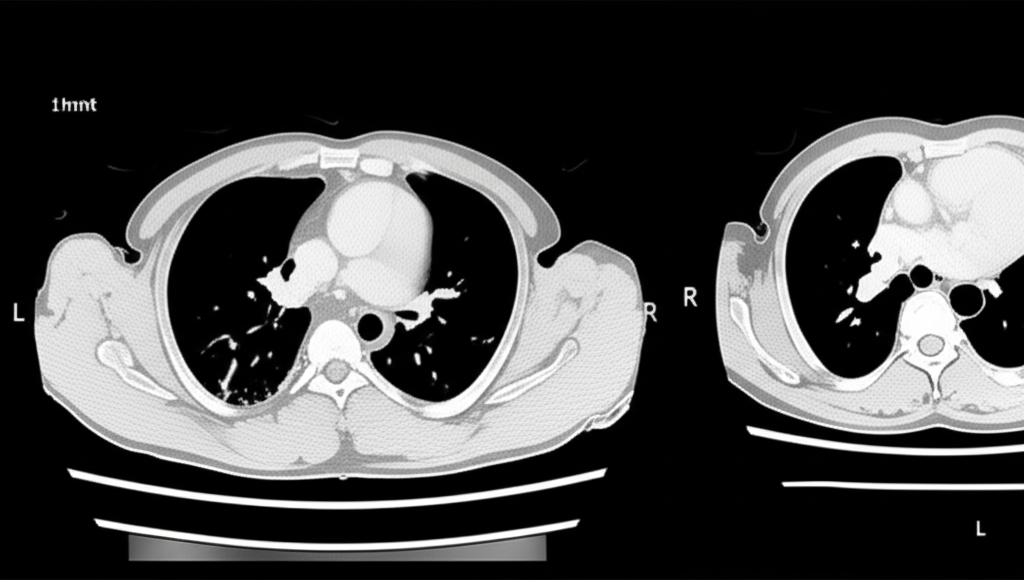

폐암 수술 전, 폐 CT는 종양의 크기, 위치, 주변 조직으로의 침범 여부 등을 정확하게 파악하는 데 사용됩니다. 이를 통해 최적의 수술 방법을 결정하고 수술 후 예후를 예측할 수 있습니다. 또한, 항암 치료나 방사선 치료 후 폐 CT를 통해 치료 효과를 평가하고 치료 계획을 조정하는 데에도 활용됩니다.

폐 CT는 폐암의 크기, 위치, 림프절 전이 여부 등을 정확하게 파악하여 병기를 결정하는 데 중요한 역할을 합니다. 조기 폐암의 경우 수술적 절제를 통해 완치를 기대할 수 있으며, 폐 CT는 이러한 조기 진단에 결정적인 기여를 합니다.

폐 CT는 폐 질환을 조기에 발견하고 정확하게 진단하는 데 매우 중요한 검사입니다. 특히 폐암의 조기 진단에 효과적이며, 다양한 폐 질환의 진단 및 치료 계획 수립에 도움을 줍니다. 건강 검진 시 폐 CT 검사를 고려하여 건강한 삶을 유지하시기 바랍니다. 정기적인 검진은 건강을 지키는 가장 확실한 방법입니다. 건강한 삶을 위해 지금 바로 폐 CT 검사를 고려해보세요.